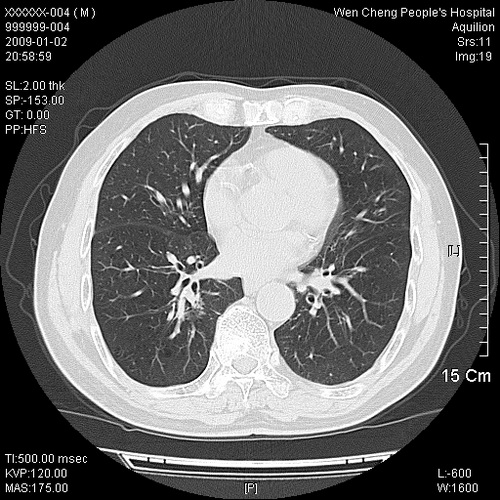

男性,73岁,有慢支病史,肿瘤系列标志物检验正常,血沉及血常规正常

右肺下叶背段小片状 磨玻璃样模糊影,内见血管及含气支气管像,支气管管壁增厚。考虑:慢性炎症!

右肺下叶背段小片状 实性与磨玻璃样影,内见血管及含气支气管像,支气管管壁增厚,边缘见长毛刺影。考虑:慢性炎症或肿瘤!建议抗炎治疗复查,密切观察随访!

右肺下叶片团状影内见扩张的含气支气管和支气管管壁增厚,其周有磨玻璃样模糊影和长毛刺。考虑慢性炎症可能性大。

2、右肺下叶片团状影内见扩张的含气支气管和支气管管壁增厚,其周有磨玻璃样模糊影和长毛刺。考虑周围型肺ca可能,结核不排。

高度提示细支气管肺泡癌,建议抗炎治疗半月观察病灶变化,如无明显改变,建议立即手术治疗.

病变形态非常不好呀,临床上血常规及症状也不明显,不太支持炎性病灶,高度警惕肿瘤病变,最好做个纤支镜检查。